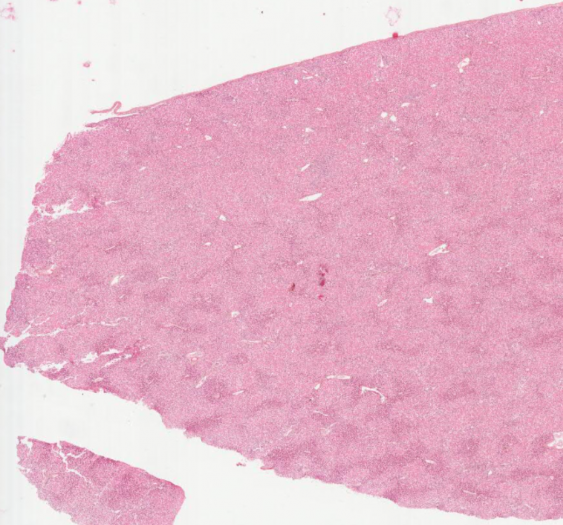

细胞和组织的适应与损伤

脂肪坏死